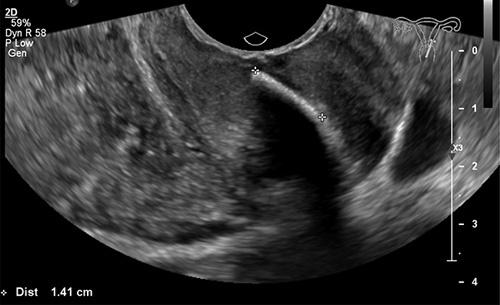

The authors present a case of a woman with the feeling of a foreign body in the vagina and a long-standing history of secondary infertility of unknown cause. She was found to have osseous metaplasia of the uterus with spontaneous expulsion of the bony fragments from the uterus into the cervical canal, creating the sensation of foreign body in the vagina. She was treated with hysteroscopic resection. Fertility returned 3 months post procedure.

作者介绍了一名女性病例,该女性有阴道异物感且有长期不明原因的继发性不孕史。她被发现患有子宫骨化生,子宫内的骨碎片自发排入宫颈管,从而产生阴道异物感。她接受了宫腔镜切除术治疗。术后3个月恢复了生育能力。